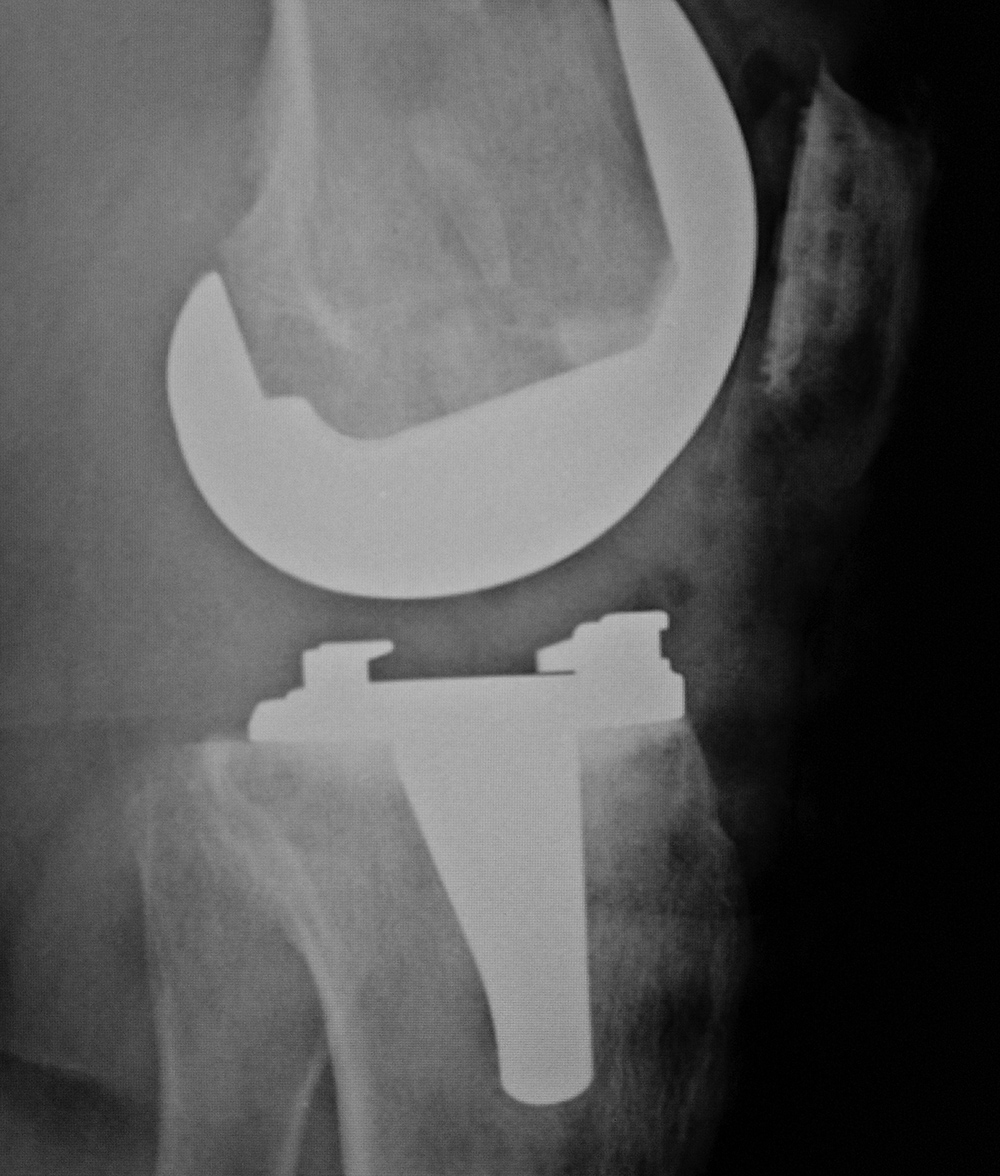

Subtle failure of total knee arthroplasty (TKA) |

A noncemented total knee arthroplasty is present with a metal backed patellar component. There is also a polyethylene locking clip which locks the tibial polyethylene into the tibial base plate. The anterior cortex of the femur is notched and eroded (top arrow). There is also subtle subsidence of the tibial component (bottom arrow). From Benjamin, 1994 |